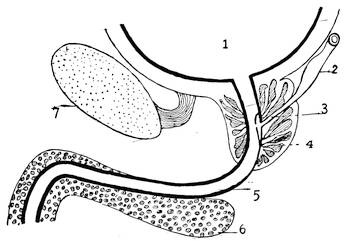

The Wolffian body, or mesonephros, appears in the shape of two longitudinal protuberances on either side of the mesentary along the spinal column. The protuberances consist of a series of transverse excretory tubules or nephrides. These tubules open into two pronephric ducts, or Wolffian ducts, which are running alongside the abdominal aorta. These two Wolffian or primitive male ducts open at the caudal end of the embryo into the hind-end of the alimentary canal, or the cloaca (Cut III, Fig. 2).

When the Wolffian body has almost reached its greatest development a second longitudinal duct makes its appearance by the evagination of the ventral surface of the Wolffian body. These ducts lie in close proximity of the Wolffian ducts, along the dorsal aspect of the coelom, or body-cavity, and are known as the ducts of Müller, or the primitive female ducts. The function of these canals in lowly organized animals is that of receiving21 from the body-cavity the ova and of evacuating them from22 the body. The Müllerian ducts also open into the cloaca. At the lower end the Müllerian and Wolffian ducts run in close apposition and form the genital cord. At this stage of development the embryo is thus hermaphroditic like the worms.

The metanephros, or the true kidney, appears first as an epithelial or renal evagination of the Wolffian duct on the dorsal side of the latter and near its opening into the intestinal canal or cloaca. This bud grows forward, extends headward toward the position of the Wolffian body and becomes a long, narrow tube, the ureter. The blind end branches into different tubules, each having a sacculated end. They soon assume a tortuous and convoluted form and represent the permanent kidney. The Wolffian body is now replaced in its function by the true kidney, and enters into special relations with the sexual organs, by being transformed into the genital apparatus of the male.

Before the Wolffian body has yet degenerated the mesothelial cells overlying the free surface of that body, at its upper part, and at the ventro-mesial side, assume a high columnar form and form an elongated swelling, known as the internal genital ridge. As the degeneration of the Wolffian body proceeds the genital ridge is differentiated into the indifferent sexual gland, by producing a projection upon the wall of the coelom or body cavity. This prominence is attached to the surface of the Wolffian body by a fold of the peritoneum. At this stage there is no distinction of sex. The sexual gland represents the indifferent type of the sexual apparatus.

While this metamorphosis is going on at the head-end of the sexual ducts, the caudal ends undergo also a certain degree of development.

In the early embryonic life the intestinal canal is in communication with the allantois. In fact, both form one continuous canal. When the caudal, pointed end of the intestine becomes obliterated, the allantois-duct on the ventral side, and the intestine on the dorsal side, both open into a kind of pouch, the cloaca. When the body-cavity of the embryo closes in the course of farther development, the allantois, which is the connecting link between the embryo and the placenta, enters the embryo by the small opening known as the umbilicus. Very soon the middle23 segment of the intra-embryonic allantois dilates and assumes the form of a spindle-shaped sac, the later urinary bladder. The portion of the intra-embryonic allantois, connecting the summit of the bladder with the umbilicus, soon becomes an impervious cord, known as the urachus. The portion of the allantois intervening between the bladder and the intestine is designated as Sinus Urogenitalis.

Into this sinus opens the short canal, connecting the lower end of the bladder with the upper end of the urogenital sinus which becomes later on the urethra. The sinus also receives the genital ducts, the Müllerian and the Wolffian ducts, and the latter’s evaginations, the ureters. Later on, owing to alterations through unequal growth, the orifices of the ureters, which originally lie in close apposition with the openings of the Wolffian ducts, change their position and are moved toward the bladder. The interval between the two pairs of ducts, the Wolffian ducts and the ureters, increases, until the ureters finally open into the bladder.

The intra-embryonic allantois has thus furnished the following organs: the solid cord urachus, or ligamentum vesico-umbilicale, the urinary bladder, the urethra and the urogenital sinus. The latter is still in communication with the intestine by means of the cloaca.

At the next step ridges or folds spring from each side of the cloaca, grow toward each other, until they finally coalesce and form a complete septum. By farther development the original epithelial septum becomes the permanent perineum. Since the intestine is now no longer in communication with the urogenital sinus, the cloaca as such disappears. At this stage the intestine ends in a blind sac. It is closed up towards the exterior by the anal membrane. Neither are urethra and genital canal in communication with the exterior. They both open into the urogenital sinus, and the latter is closed up towards the exterior by the urogenital membrane. The anal membrane soon breaks through and the rectum opens to the exterior by the way of the anus.

The genital portion of the Wolffian body persists in the male in its entirety and serves as the efferent ducts of the testis. They open into the upper part of the Wolffian duct. The latter is retained complete. The portion nearest the testis is thrown into coils and forms a part of the epididymis, the remainder is converted into the vas deferens and the ductus ejaculatorius and the lateral outpouching of the wall, the vesicula seminalis.

The Müllerian ducts disappear completely in the male. Only the lower ends of the ducts fuse to form the sinus pocularis, or utriculus prostaticus.